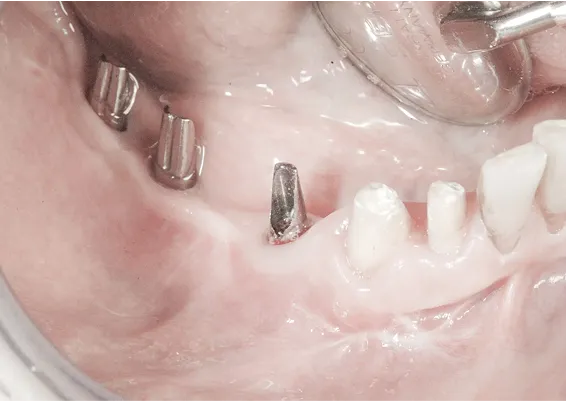

OSTEOTOMIA - ROZSZCZEPIENIE WYROSTKA ZĘBODOŁOWEGO

To technika pionowego rozszczepienia wyrostka zębodołowego przy użyciu osteotomów. Jest to delikatna technika zabiegowa stosowana w sytuacji braku dostatecznej ilości kości na szerokość. Polega na rozszczepieniu pionowym zanikłego w wymiarze horyzontalnym/poprzecznym wyrostka zębodołowego.

Zabiegu rozszczepienia dokonuje się przy użyciu Piezosurgery, specjalnych zestawów osteotomów lub dłut, którymi rozcina się i rozchyla kość zanikłej części zębodołowej żuchwy lub szczęk.

Pomiędzy rozchylone okładki kostne wprowadza się implanty, uzupełniając materiałem kościotwórczym pozostałą szczelinę w wyrostku. Należy w sposób właściwy dobierać i kalibrować instrumentarium, by nie spowodować uszkodzeń związanych z odłamaniem rozszczepianego fragmentu kostnego.